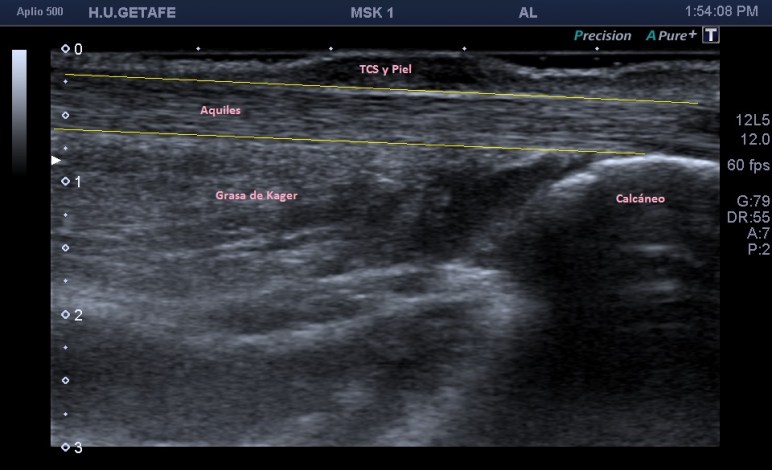

Nuestro objetivo es ver esto:

Normalidad, en la imagen 1 y 2 ves un aquiles normal.

Las imágenes 1 y 2 son la normalidad, es lo que casi nunca solemos ver en este tipo de estudios, pero en ocasiones sí, y como además cuando realizamos este protocolo, siempre es recomendable explorar lado contralateral, podemos muchas veces comparar la región patológica con la normal. El aquiles lo estudiamos siempre en toda su longitud, desde la inserción hasta su origen, en eje corto y en eje largo. Fijándonos bien en toda la ecoestructura posterior de la pierna y estudiando la profundidad de la grasa de Kager.

Las fibras del tendón son alargadas, lineales, tensas con las flexión dorsal.

Ojo con la anisotropía, la hipoecogenicidad producida el ligero cambio de angulación del tendón cuando inserta en el calcáneo posterior…La clave, hiperflexión dorsal, mucho gel y amoldar la posición de la sonda para estudiar estas fibras insercionales.